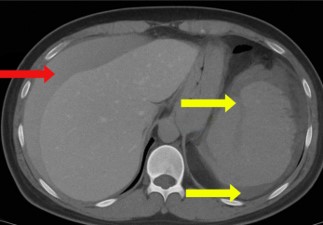

One day after the procedure, she visited the emergency department following three episodes of hematochezia and multiple episodes of near-syncope without loss of consciousness. She presented with intense abdominal discomfort, hypotension (BP=84/59 mmHg), and tachycardia (HR=110 bpm). A CT scan of the abdomen revealed a grade four splenic lesion in the middle third and free fluid in the splenic and perihepatic spaces (Figures 1 and 2).

Figure 2: Coronal computed tomography scan showing the presence of free fluid in the splenic and hepatic spaces.